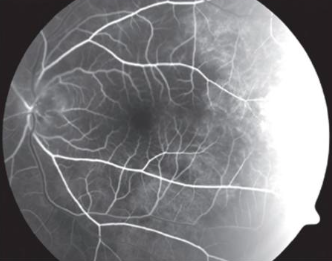

• A large subhyaloid hemorrhage in the inferior macula, resulting in blockage of both retinal and choroidal fluorescence.

There is also a subretinal hemorrhage along the superotemporal arcade. Note how only choroidal fluorescence is blocked, with overlying retinal vessels still visible due to the location of the bleed.